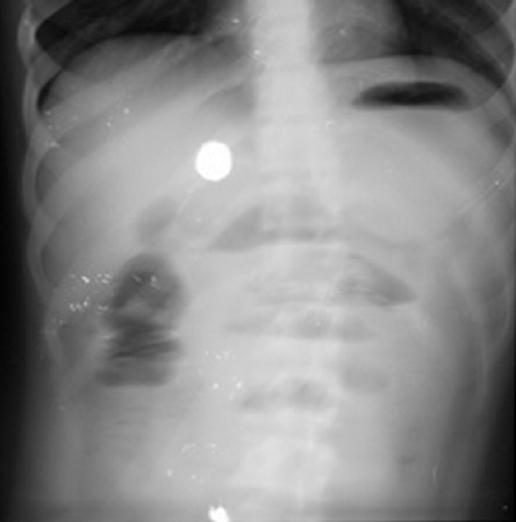

A 14-year-old boy with cerebral palsy and medical history of foreign body ingestion was admitted to the emergency department due to intractable vomiting. The patient presented with a 2-day history of the inability to defecate, retch, nausea, bilious vomiting, restlessness, and abdominal pain. On abdominal examination, tenderness was observed. There was no gas and stool output after the rectal enema. At the admission, body temperature: 37.5°C, blood pressure: 110/76 mmHg, heart rate: 96/min, C-reactive protein: 1.25 mg/dL, WBC: 22.74, and NEU: 20.9. The X-ray revealed an air-fluid level with partial obstruction (Fig. 1).